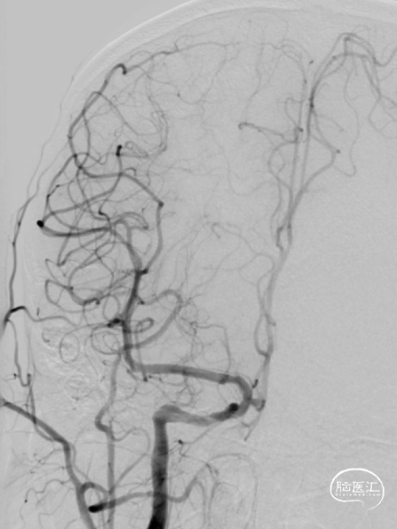

沿导丝置入5*30mm AVIATOR PLUS球囊扩张颈内动脉开口处狭窄病变,后将9*40mm PRECISE支架送至狭窄处释放。再次造影可见右侧颈内动脉血流通畅,但仍有50%左右残余狭窄。

3

再次应用6*30mmAVIATOR PLUS球囊后扩张,此时患者出现轻度颈动脉窦反应。造影示残余狭窄约30%,支架贴壁良好,血流通畅,颅内血流速度尚可。

4

观察患者体征稳定,支架形态良好,撤出器材,使用Exoseal封堵止血系统封堵股动脉穿刺点后,结束手术。患者愈后良好